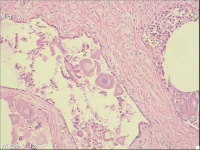

性别

男

年龄

56岁

前列腺增生

前列腺turp切除

灰白条状组织1堆,大小5x4x2cm。

前列腺增生腺管腔有这种形态很常见。

有些不在腺管里,感觉像钙化。

考虑符合:慢性前列腺炎伴腺体增生及淀粉小体形成。